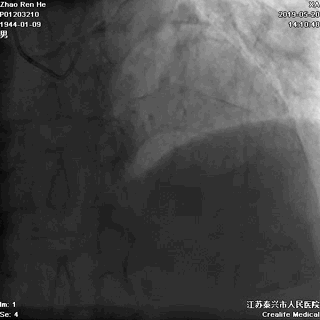

右冠几乎齐根闭塞

右向左无侧枝循环

RCA几乎齐根闭塞,非锥形残端

闭塞入口处有分支发出

闭塞出口处发出分支血管

CTO闭塞段长度小于20mm